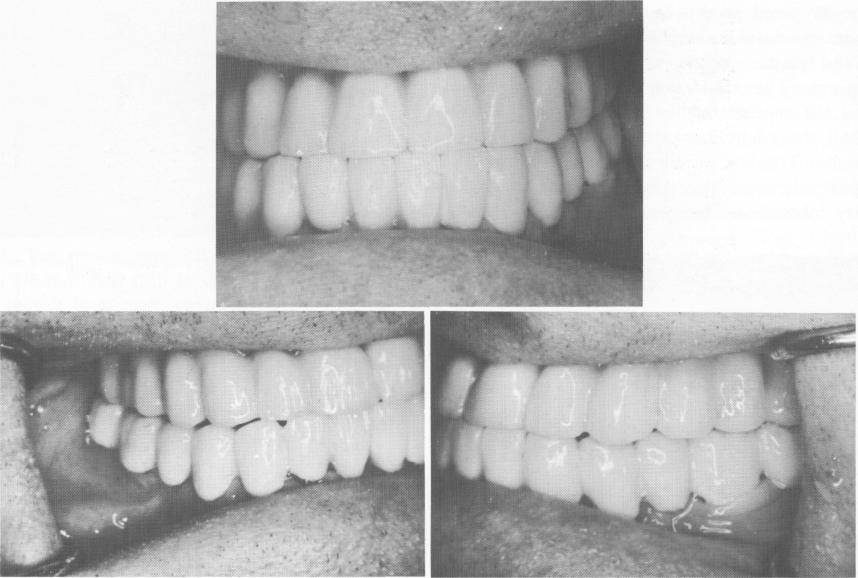

Fig. 15-36. The completed case, showing the teeth to be in a Class I relationship.

1 Case shows  teeth in Class I relationship after blade implantation